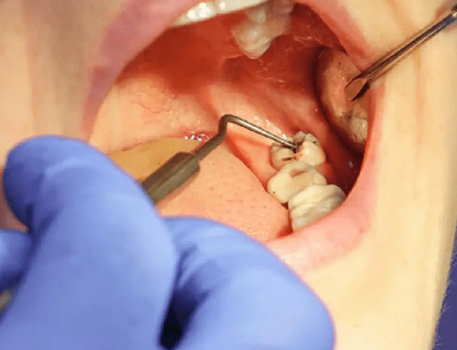

1. Expert Consultation & Diagnosis

Comprehensive oral examination with digital X-rays to assess the position and condition of your wisdom teeth.

Personalized treatment planning based on your specific needs.